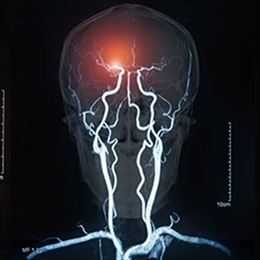

Нейроангиография относится к визуализации кровеносных сосудов центральной нервной системы.

Нейроангиография позволяет диагностировать и лечить широкий спектр заболеваний, включая как экстракраниальные (вертебробазилярная недостаточность, стеноз сонных артерий), так и интракраниальные (аневризмы артерий центральной нервной системы, артериовенозные мальформации, инсульт, эмболизация опухоли) заболевания.